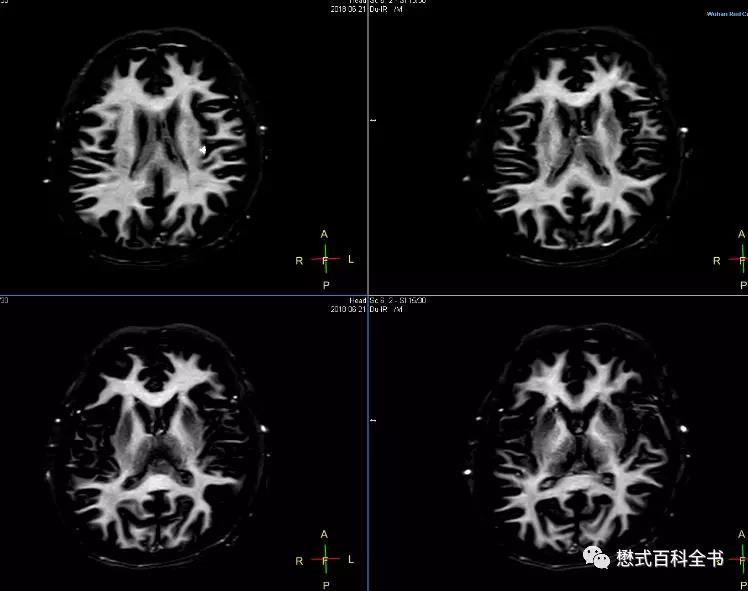

采用连续两个反转脉冲作为准备部分的反转恢复序列又叫做双反转序列(Dual IR)。在双反转序列中就存在两个反转时间(TI1和TI2),通过合理的设置这两个时间可以选择性的抑制两种组织,比如在头颅扫描中,可以通过抑制脑脊液和脑白质信号达到脑灰质成像(Grey Matter only image)的目的,或者抑制脑脊液和脑灰质信号来实现脑白质成像(White Matter only image)。

前面也介绍了脑灰白质成像的专用序列,其实就是采用双反转序列,通过两次反转选择性的抑制两种组织,从而达到只进行某一种组织的成像效果。

在飞利浦中,原始序列里有专门的脑灰质成像(Grey Matter only)序列和脑白质成像(White Matter only)序列。理论上,1.5T和3.0T由于组织的T1值不同,这个参数有变化,但是我发现,1.5T和3.0T基本上参数设置是一致的。脑灰质成像(Grey Matter only)序列

脑白质成像(White Matter only)序列TR=14489ms或者15000ms,大于14000ms,因为脑白质成像的TI时间不同;TE=25ms或者20ms;可以看出,脑白质成像序列的参数中,两个反转时间TI1和TI2都比脑灰质的长,所以自然脑白质成像序列的TR很长。而且根据经验,脑白质成像的扫描时间比灰质成像长,而且效果没有脑灰质好,仔细看会发现有一点勾边。这是无论如何怎么调都调不下去的。这和要选择性进行脑白质成像,选择的两个TI有关。